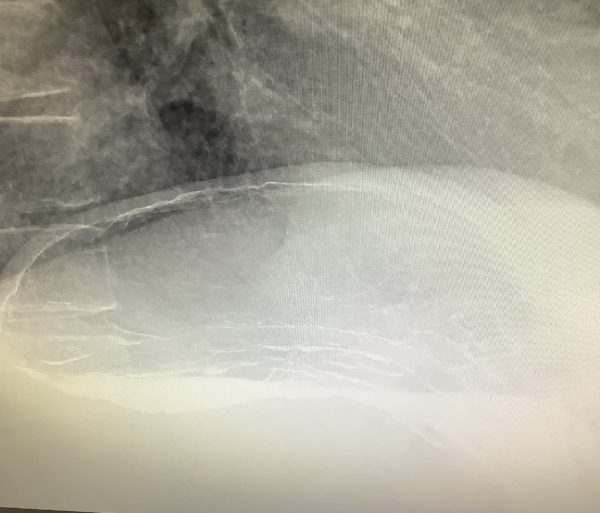

胃の検査について

バリウムの検査で飲んでいただくものでバリウムと発泡剤があります。

発泡剤についてお話しします。

発泡剤を飲むことで胃を風船みたいに膨らませるころができます。

発泡剤の抜けた胃が上の胃

発泡剤を追加して膨らませたのが下の胃になります。

ゲップを我慢していただくのはこのように差があるからです。なるべく我慢していただいて

出てしまったら追加で飲んでいただきますのでよろしくお願いします。

バリウムが苦手で発泡剤が飲みにくいなどありましたらご相談ください。

お水で飲んでいただくこともできます。

胃の検査は苦手だと思うんですが頑張って頂きたいと思います。